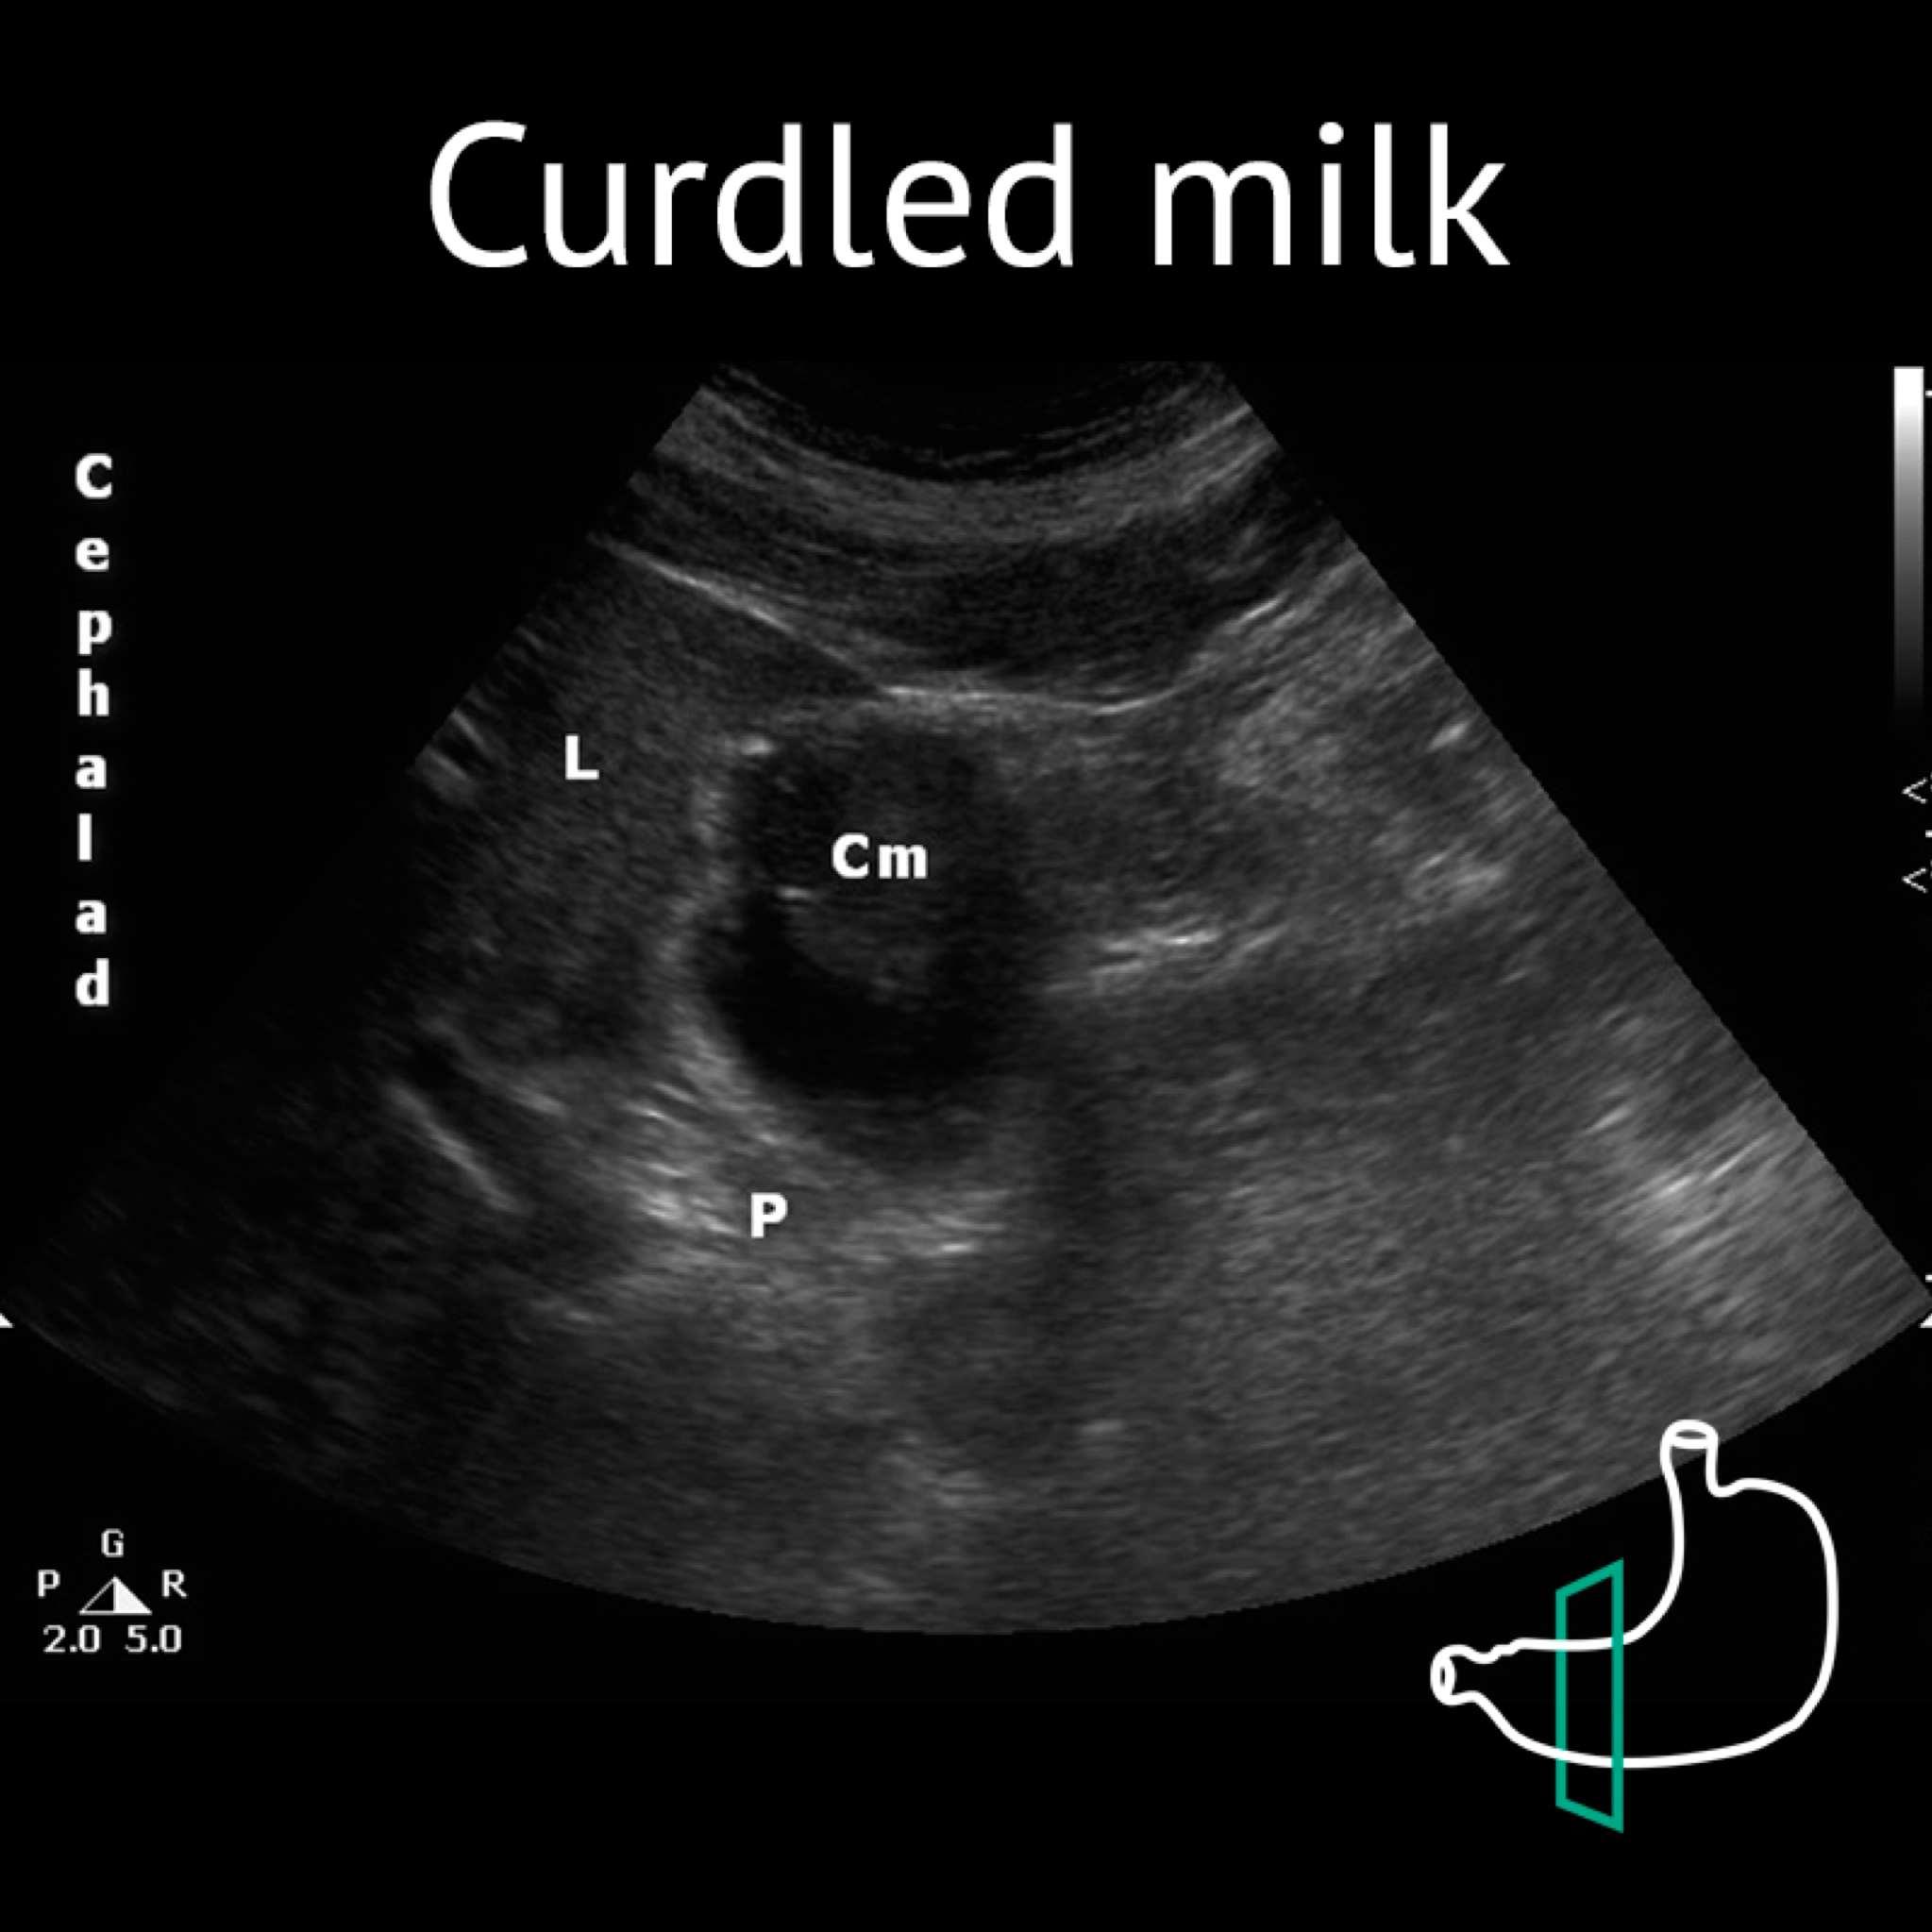

Cm: curdled milk; L: liver; P: pancreas